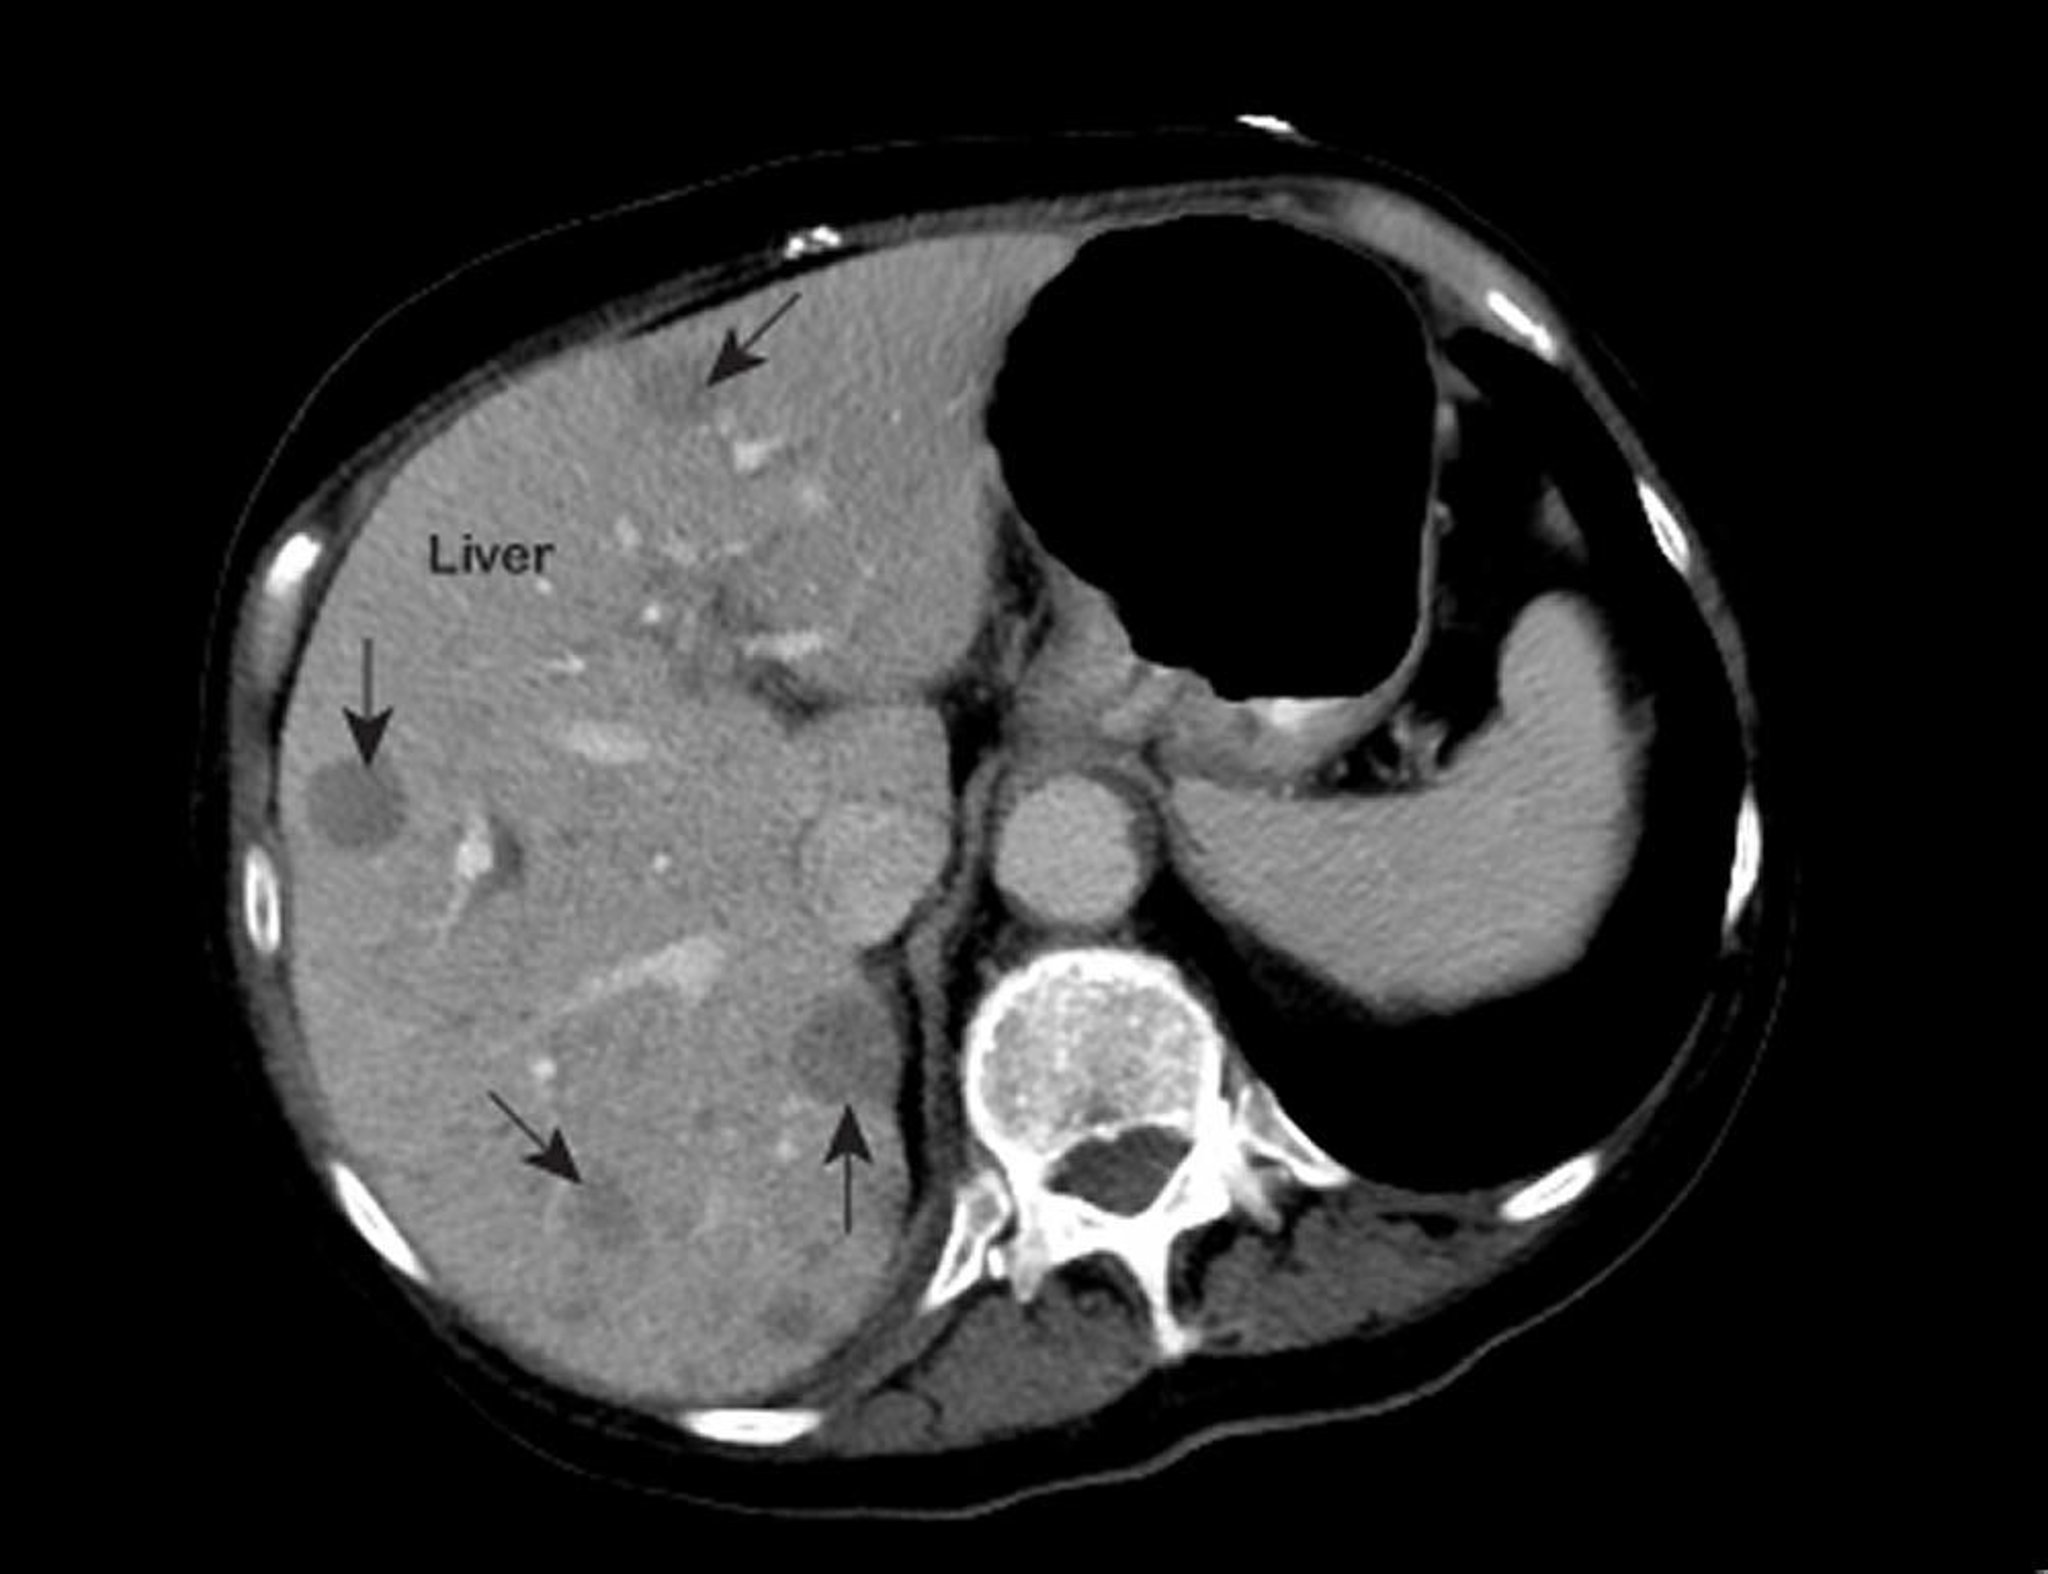

Metastasen der Leber

Ein auffälliges MRT des Brustkorbs zeigt Bereiche mit geringer Abschwächung (mit Pfeilen markiert) innerhalb der Leber. Dieses Erscheinungsbild ist typisch für metastasierenden Leberkrebs.

Photo courtesy of Patrick O’Kane, MD.